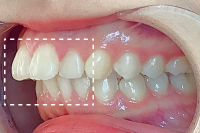

Basicプラン

上下前歯12本の部分矯正

20代 女性

治療費用:Basic 33万円(税込)

治療期間:4ヶ月

- Before

After